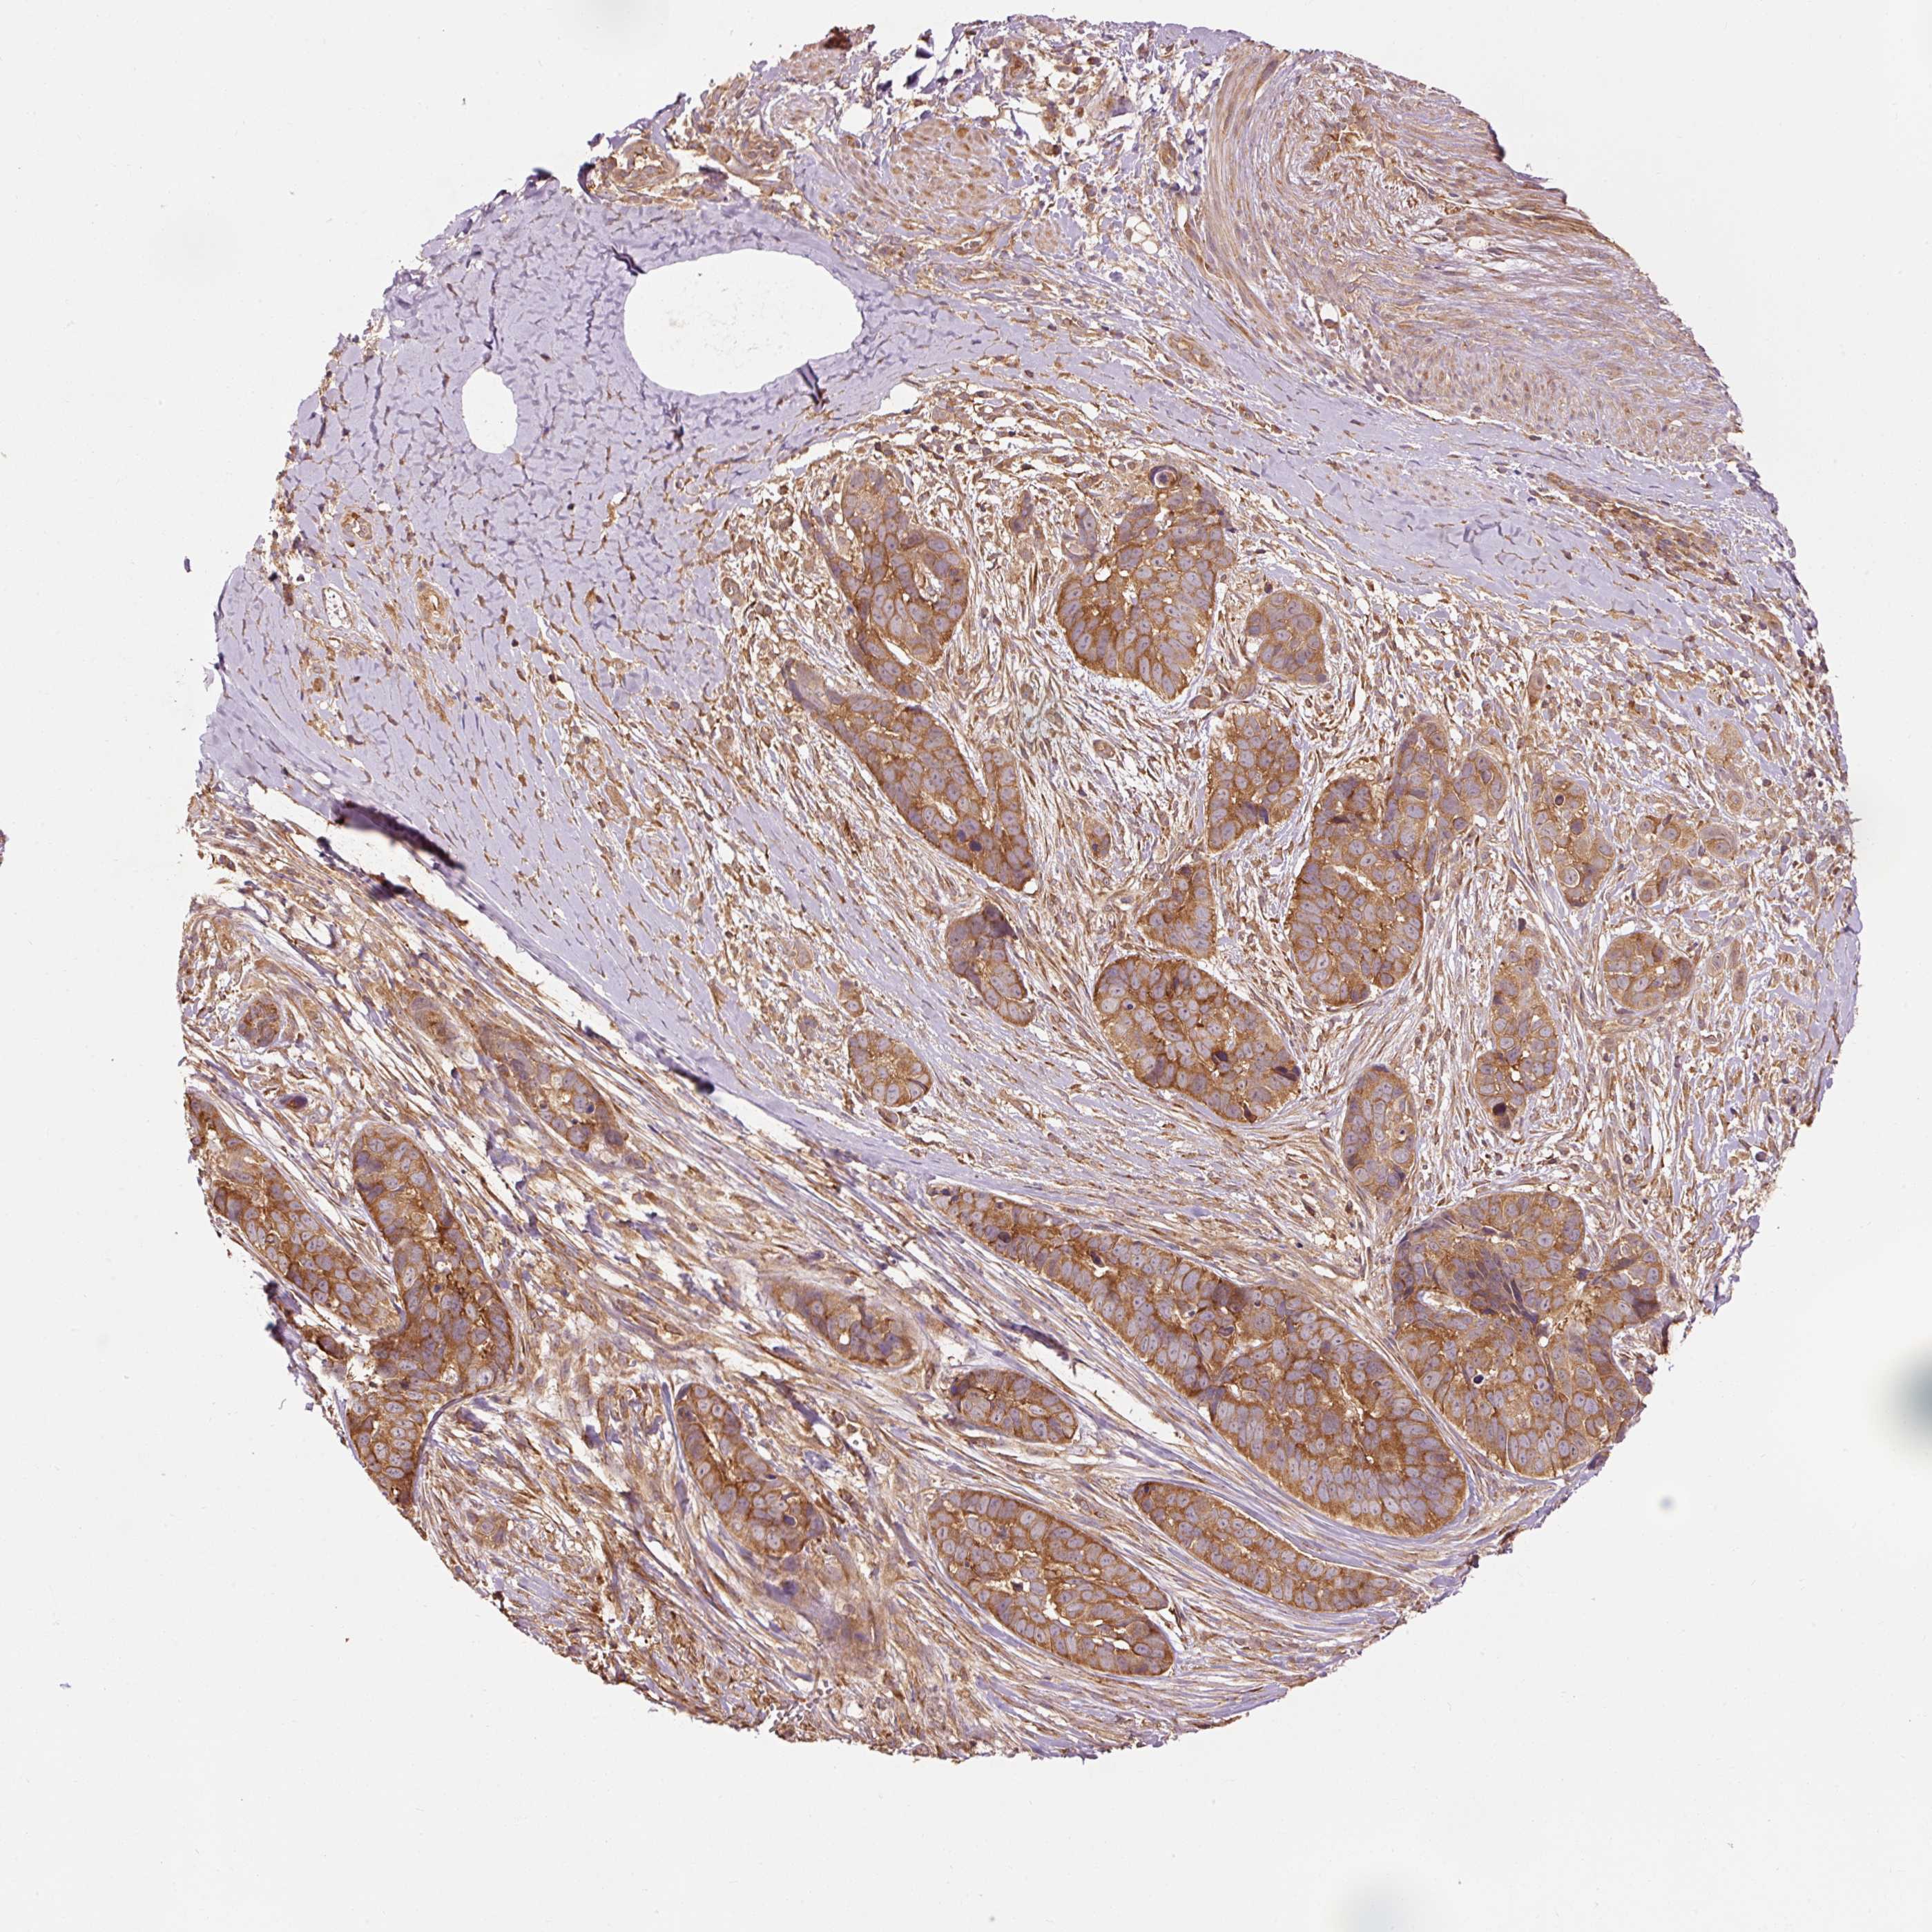

SKIN CANCER - Protein expressioni

A mouse-over function shows sample information and annotation data. Click on an image to view it in a full screen mode. Samples can be filtered based on level of antibody staining by selecting one or several of the following categories: high, medium, low and not detected. The assay and annotation is described here.

Antibody staining in the annotated cell types in the current human tissue is reported as not detected, low, medium, or high, based on conventional immunohistochemistry profiling in selected tissues. This score is based on the combination of the staining intensity and fraction of stained cells.

Each image is clickable and will lead to virtual microscopy that enables deeper exploration of all samples and also displays staining intensity scores, fraction scores and subcellular localization as well as patient and tissue information for each sample.

Antibody HPA060836

Squamous cell carcinoma, NOS